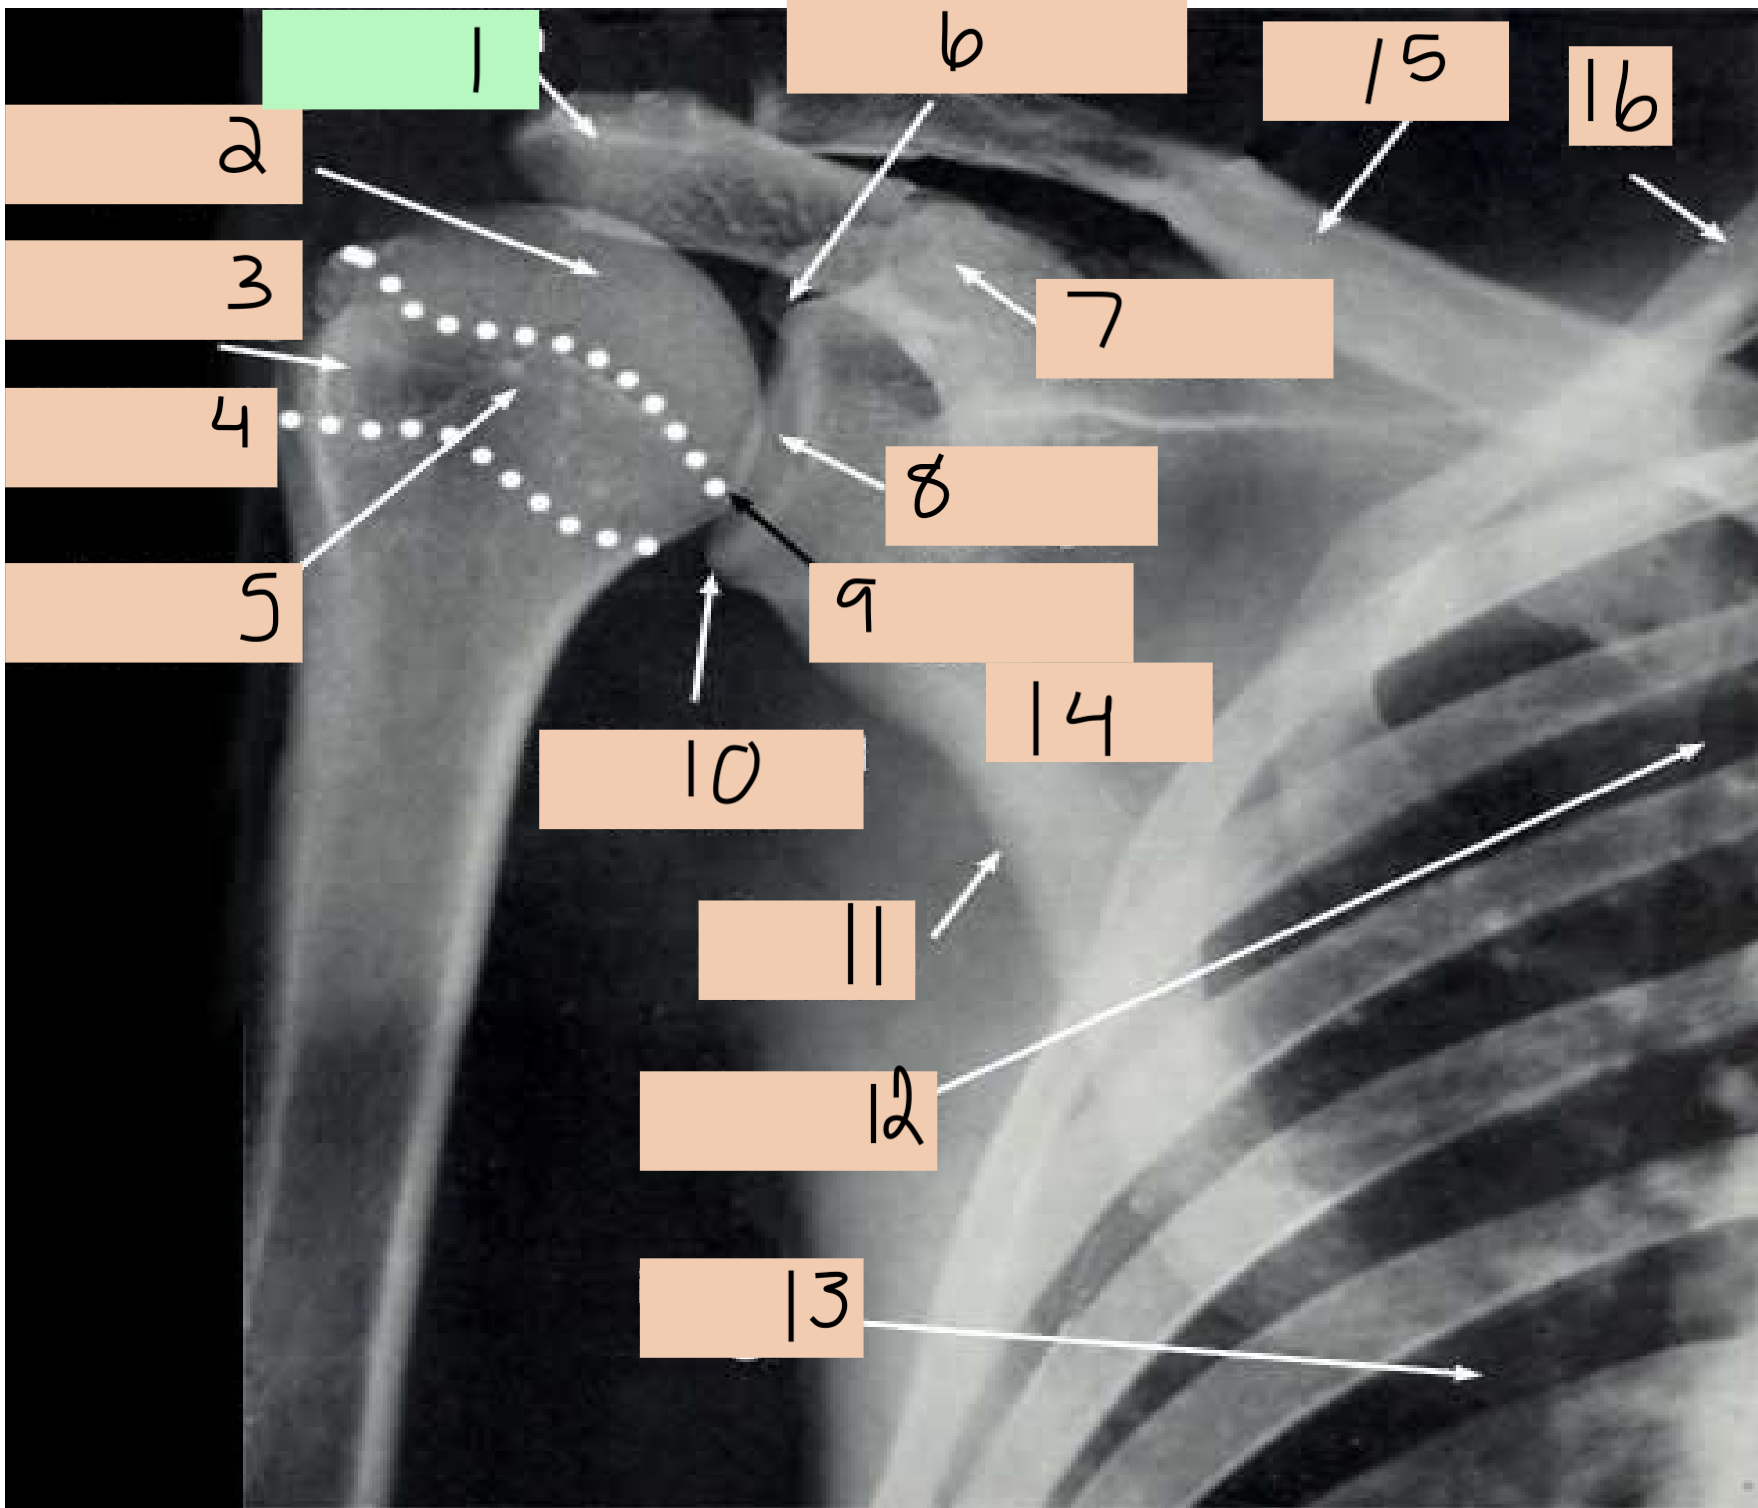

1

acromium process

2

head humerus

3

greater tuberosity

4

surgical neck

5

lesser tuberosity

6

supraglenoid tubercle

7

coracoid process

8

glenoid cavity

9

anatomical neck

10

infraglenoid tubercle

11

lateral border scapula

12

medial border scapula

13

inferior angle of scapula

14

scapula

15

clavicle